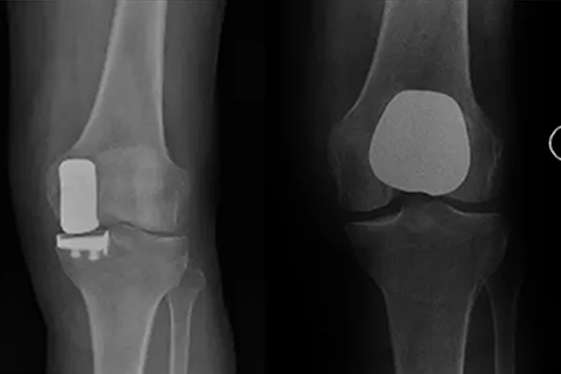

Partial Knee Replacement

If your arthritis is limited to only one part of your knee joint, a partial knee replacement could be a better option for you. It conserves bone and preserves the ligament and muscle which results in less pain, faster recovery, better function, and early discharge after surgery. Get in touch with us to know if your case is suitable for a partial knee replacement.